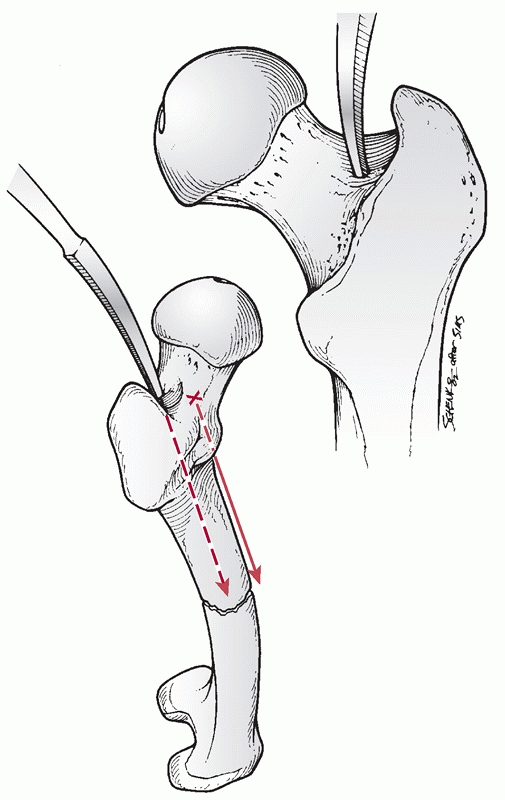

More recently, alternative antegrade intramedullary nail starting

points have been introduced. This includes starting points at, medial

to, and lateral to the tip of the greater trochanter.